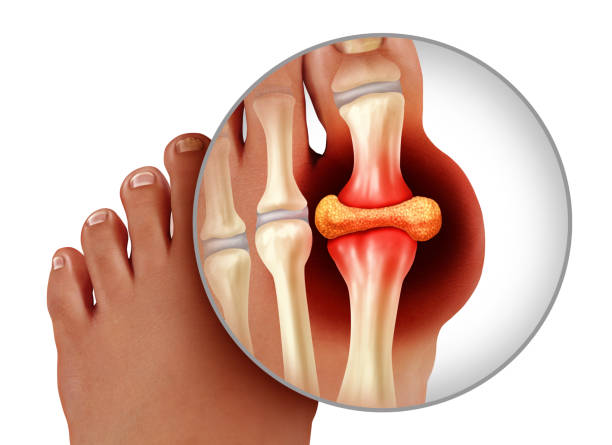

급성 통풍성 관절염은 한 개 관절에서만 나타나는데 아무래도 그 부위는 엄지발가락에서 나타나며 발 관절인 발등, 발목, 무릎 그리고 나아가서는 손목에서도 나타납니다. 통풍이 발현하면 10일 정도 지속되는데 완화가 되더라도 재발 및 악화되는 경우가 있어 치료를 받아야 합니다. 간헐기 통풍은 일반적으로 6개월에서 2년 사이 두 번째 발작이 나타나는데 통풍 발작은 치료를 받지 않으면 그 가능성이 높아져 시간이 지나면 여러 관절들로 퍼질 수 있어 반드시 치료를 받아야 하며 평상시 요산 수치를 조절해야 합니다.